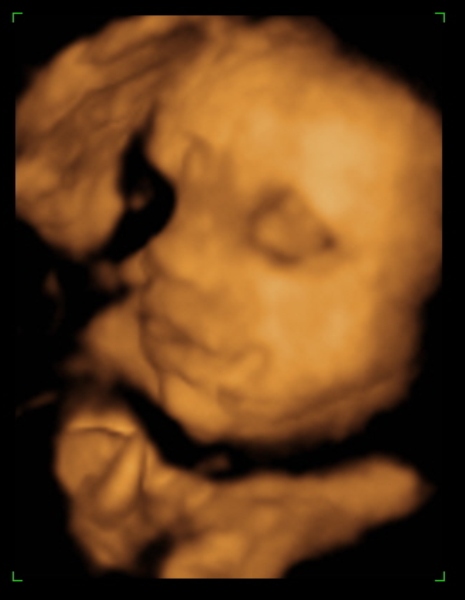

Tegnap megjártuk a 4D-t, nagyon szép husis a kisasszony :lol: persze aludt, nem kommunikált velünk, akármit ettem, ittam, csináltam. :lol: De azért féloldalasan aludt, úgyhogy csak láthattuk, volt mosoly, ásítás, fintor :lol: :lol:

Ja, és itt is megállapították, hogy nagy a talpa :lol: :lol: :lol: És a fejecskéje is, úgyhogy azt mondták majd megdolgoztat szülésnél, gondoltam "tök jó" :lol: :roll:

Méretek:

BPD - 8,17 cm

HC - 31,02 cm

AC - 28,59 cm

FL - 6,36 cm

Tappancs - 7,1 cm :lol: :lol: (s azt mondta a nő, hogy a talp általában ugyan akkora, mint az FL, tehát Dorkáé, nagy pacsker :lol: )

Becsült súly: 2078 gramm

Azt mondta, hogy ha 40 hétig bent marad, akkor 3400-3600 gramm körüli baba lesz. És tankönyv szerint halad gyarapodásban :lol: . Jaaa, és lesz haja:lol:

Ja, és a képek lemaradtak :D

Kép mosolygom:)

Kép ásítok, UFO nyitott szemeimmel:))))

Kép profilból

Kép nagy tapppppancsom:)

Persze a kis keze mindenhol ott van :lol: Bocsi, ha picit sok voltam :oops: 8)